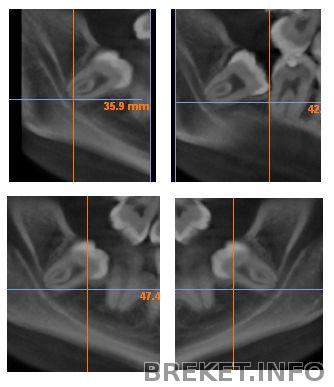

Lady Mouse У меня тоже перекос. Планирую на след.приеме объяснять это орту с помощью таких фото (орт хочет снять НЧ через пару недель):

У меня вообще похожая ситуация: перекос, одностороннее ношение тяг, контакты хорошие только с одной стороны. Может быть мне уже кажется, но даже двойки у нас похоже стоят: на разной высоте относительно 1-ек и под разными углами.

StacyJohn Думаю, не кажется... Что двойка одна чуууть развернута, мне казалось ещё год назад, но и на это орт ответила "нет, всё ровно!"... Не, она молодец тем, что без осложнений и правильными методами практически исправила мне зубной ряд. Но вот касаемо эстетики - видимо, это не к ней... О желании чуть сепарнуть трапециевидные 1ки и придать схожую форму разным двойкам я даже не знаю как ей сообщить... Думаю, нам обеим в любом случае стоит проконсультироваться у других ортов, чтобы либо услышать "всё можно сделать красивее", либо - "в вашем случае это максимум". И действовать соответствующе...